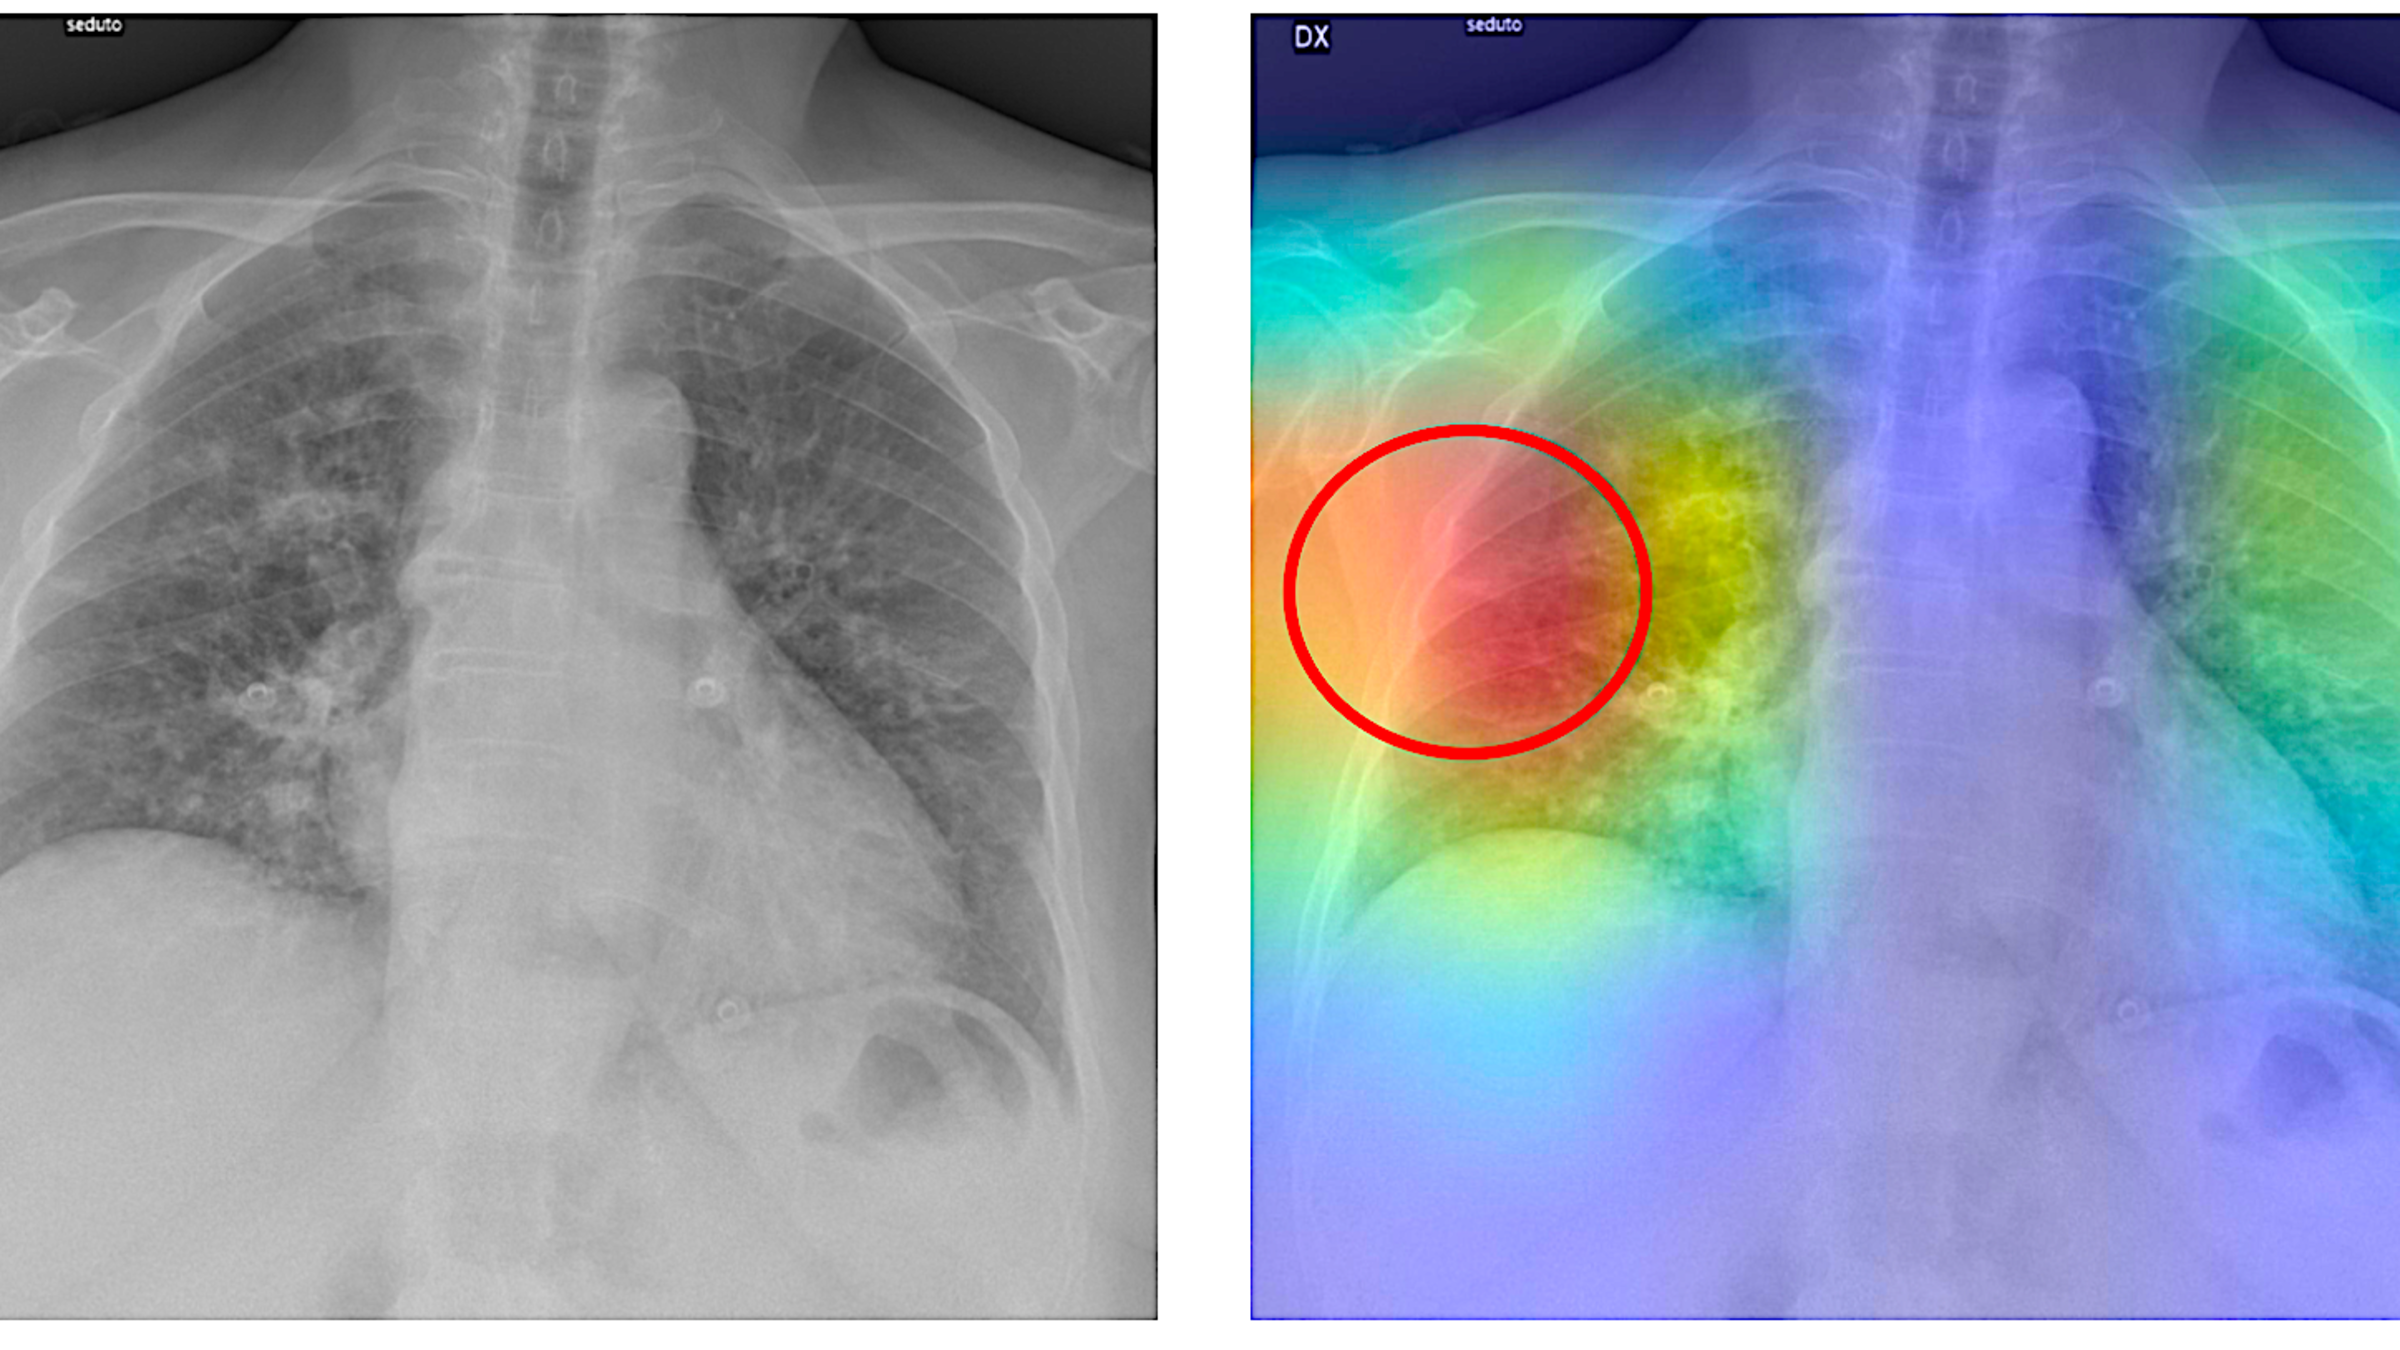

In early tests, the duo’s new AI-powered prediction system (known as RAIDER, for Rapid AI Diagnosis at Edge using Ensemble Models for Radiology) has proven highly accurate at flagging both COVID and pneumonia cases from X-rays. It’s also compact, produces rapid diagnoses and doesn’t use much power.

“We believe this model could help physicians quickly identify and diagnose both known and newly emerging respiratory diseases from chest radiographs,” says Wang, “providing high precision with minimal system requirements.”

“We were surprised by the high accuracy and low latency. The two learning networks in this small pilot study proved to be 97% to 98% accurate at diagnosing COVID-19 and viral pneumonia,” explains Wang. “That’s far better than the 60% to 70%, for example, accuracy of PCR testing for COVID.”